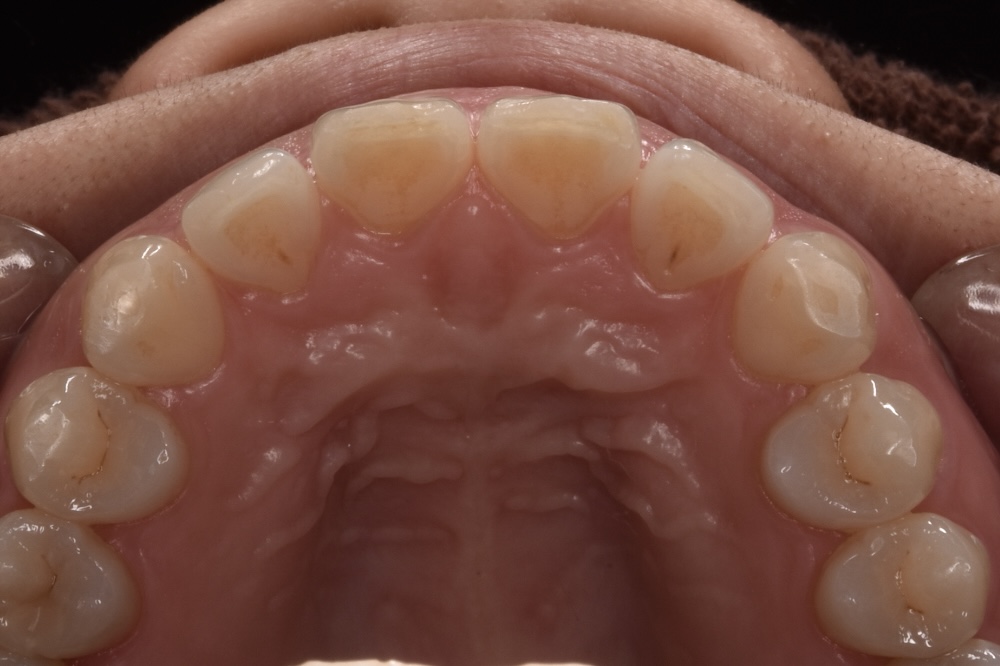

すきっ歯の改善を矯正治療でおこなった例です

モニター1 インビザラインライトプランで治療 治療期間14週間(約3・5ヶ月)

治療後